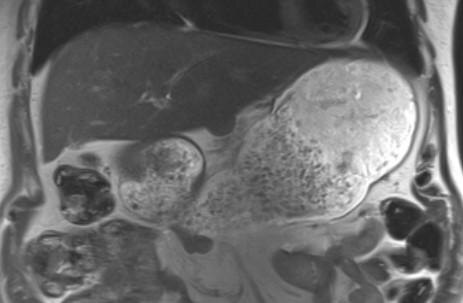

Редко их вижу, но вчера попалась добавочная доля печени🤓